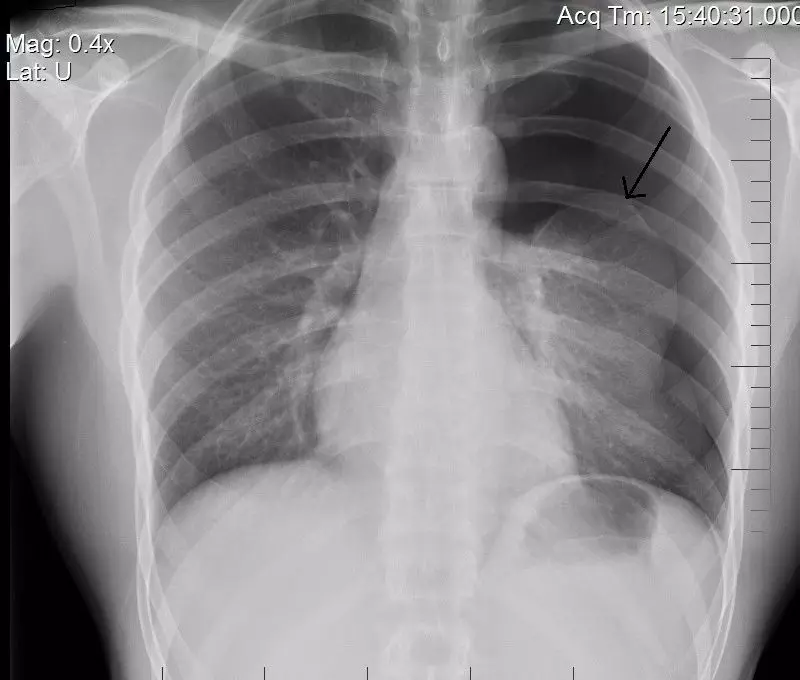

1. Anatomy of the Respiratory System